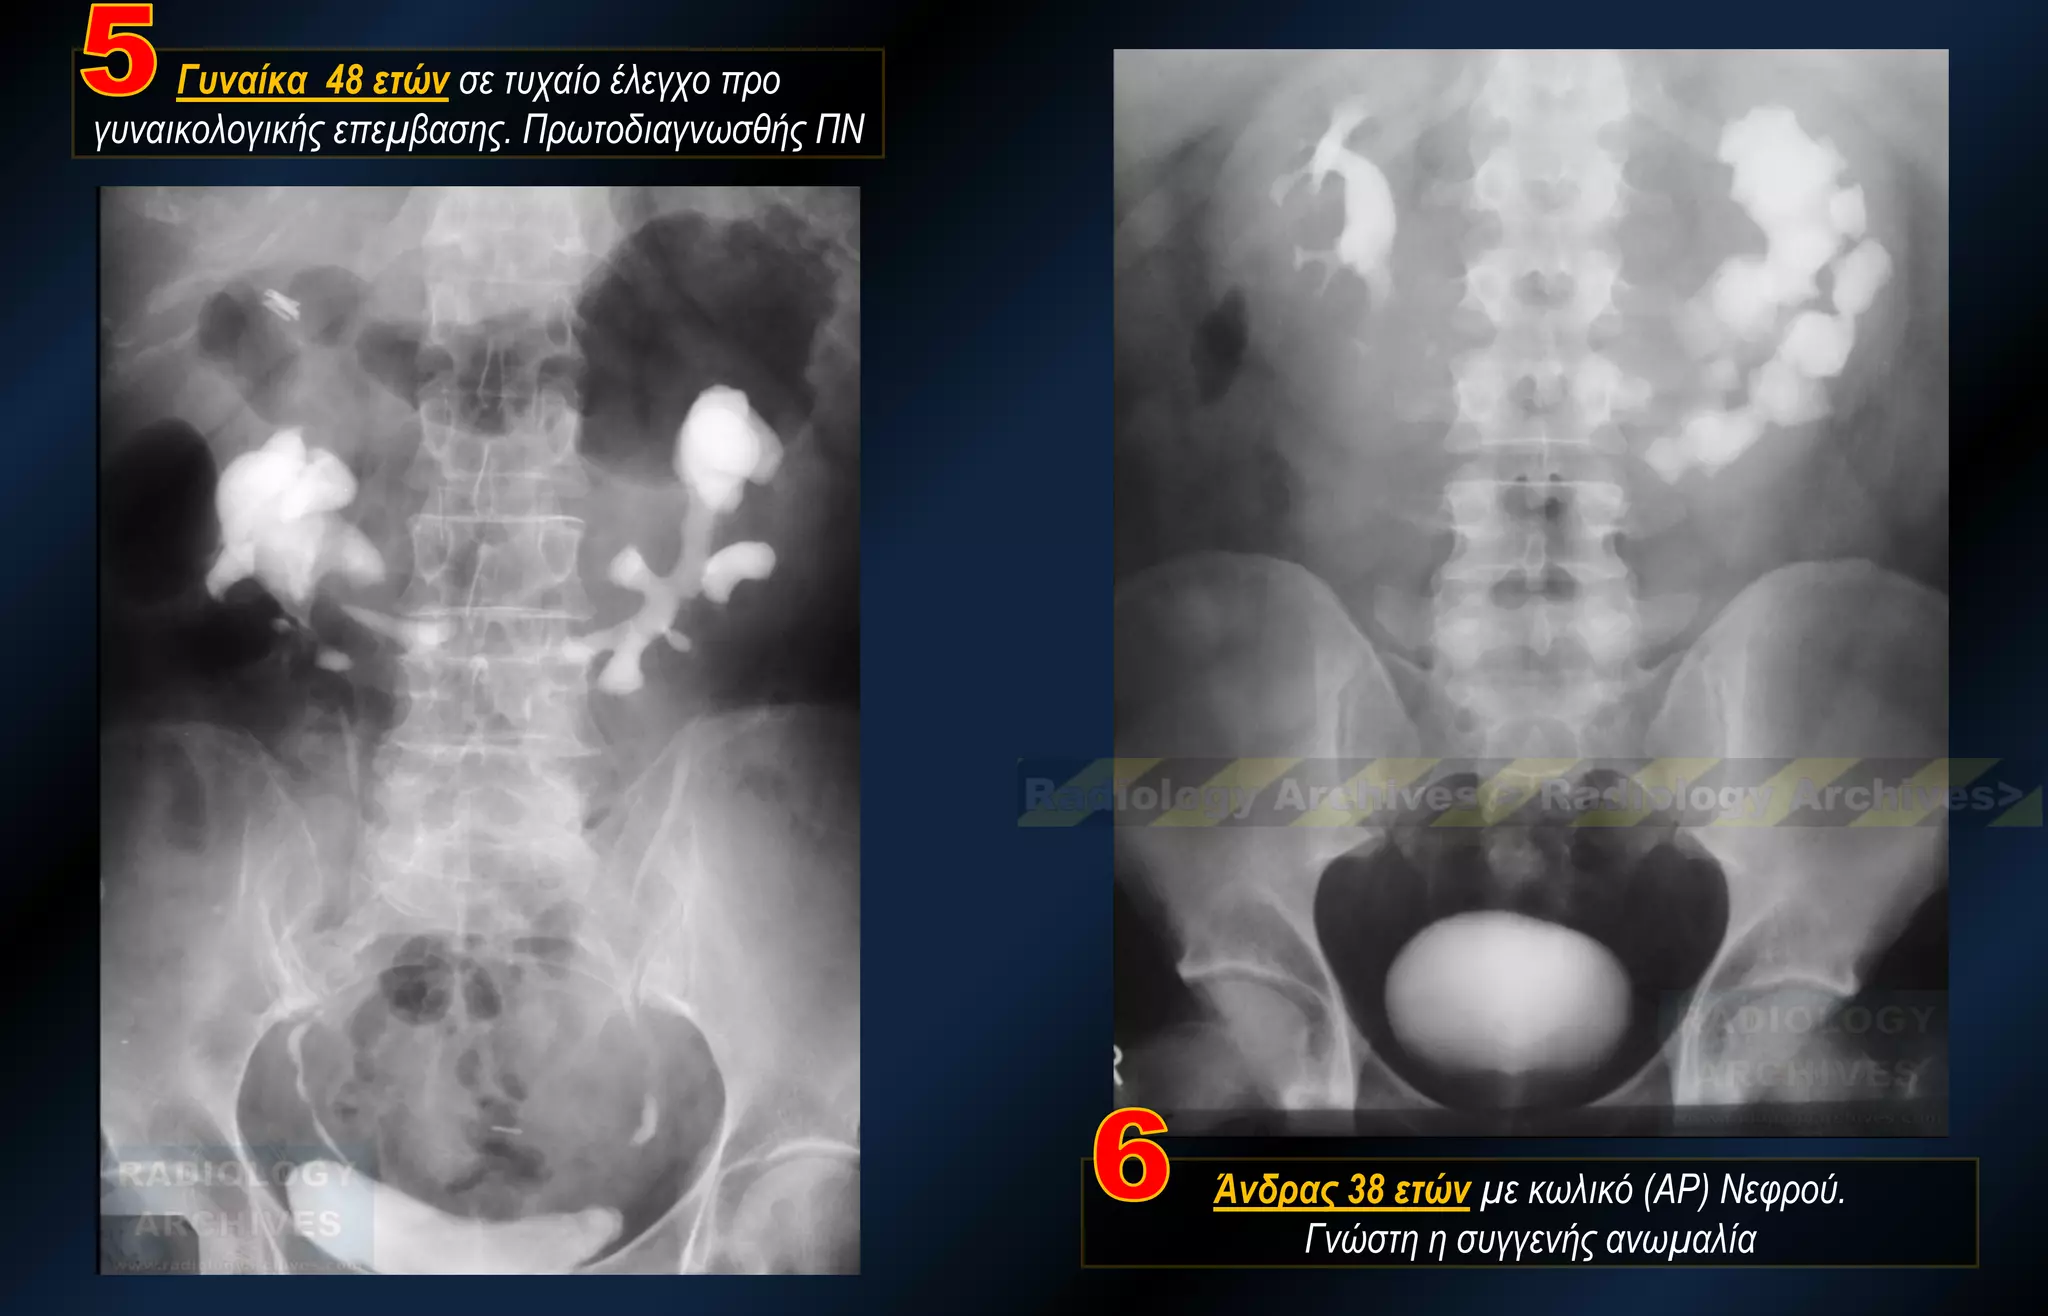

Γυναίκα 48 ετών σε τυχαίο έλεγχο προ γυναικολογικής επεμβασης. Πρωτοδιαγνωσθής ΠΝ

Άνδρας 38 ετών με κωλικό (ΑΡ) Νεφρού. Γνώστη η συγγενής ανωμαλία

Γυναίκα 48 ετώνσε τυχαίο έλεγχο προ γυναικολογικής επεμβασης. Πρωτοδιαγνωσθής ΠΝ Άνδρας 38 ετών με κωλικό (ΑΡ) Νεφρού. Γνώστη η συγγενής ανωμαλία